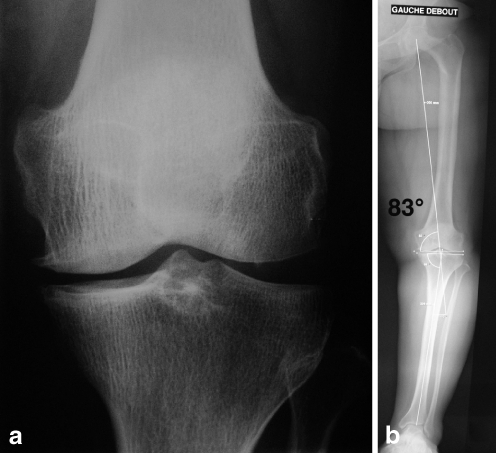

Fig. 2.

a Medial osteoarthritis appearing without severe tibial or femoral deformity. b Severe genu varum deformity of figure two case with medial femoral mechanical angle of 83° which was not predictable on standard X-ray